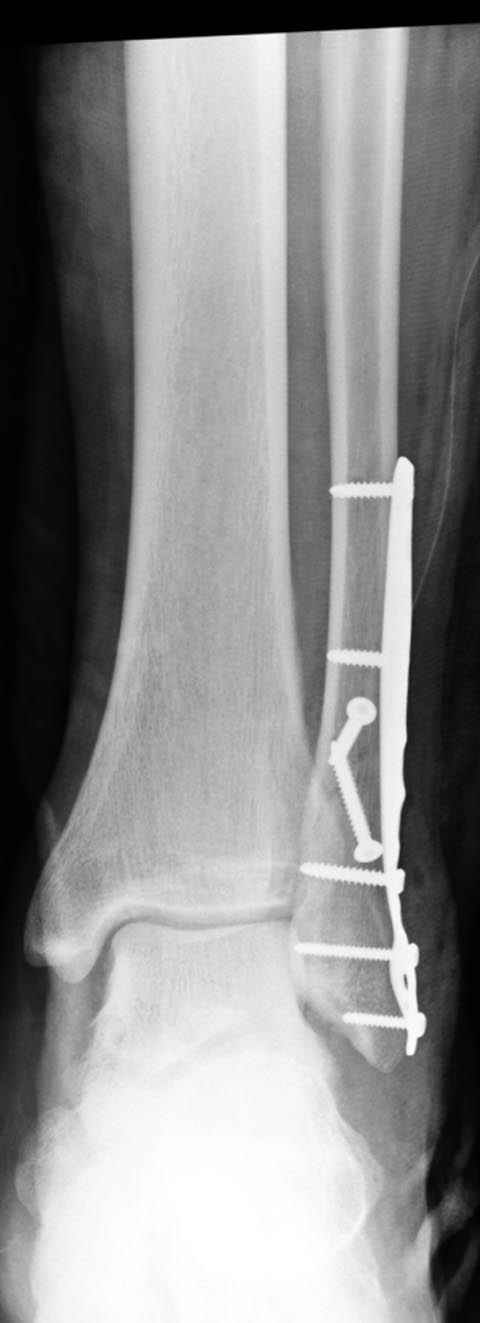

Уважаемые коллеги! Как и обещал, представляю плоды своей работы. Хвалиться особо нечем. Пошли задним

доступом сначала к м/берцовой кости, благодаря смещению линию перелома удалось сразу дифференцировать и по ней узким долотом (без молотка) мобилизовали отломки. Затем выделили задний край, там было проще пройти по линии перелома. Далее пластина по задней поверхности в дистальный отломок, винт проксимальнее пластины и дистрактором с трудом растянули отломки, ощущение было идеальной репозиции м/берцовой кости( доступен осмотр по задней и наружной поверхности), далее винты стандартно. Кстати, положение больной на боку: очень неудобно, но по-другому потом не повернуть на спину, чтобы сделать снимки в стандартных проекциях (ЭОПа нет). Затем дистрактор (два полукольца, спицы), репозиция заднего края, спонгиозный винт с шайбой, слишком проксимально, поэтому + еще один. Доступ к дельтовидной связке: рубец в передней порции, частично иссечен, шов. В общем, длительность операции 3,5 часа, а сказать, что все задуманное получилось, не могу.

А.Минервин.

Отличная, грамотная работа, поздравляю, я бы держал в гипсовой повязке до трех недель, затем разработку сустава без нагрузки, нагрузку при такой фиксации,

думаю, можно начать в 6 недель.

Все таки нужно было стянуть ДМС. Судя по снимкам остался подвывих.

Отправитель: Alexander Chelnokov 16 Март 2006, 17:18

Да все прилично получилось, и случай ведь запоздалый, так что все труднее было, чем обычно. Так что присоединяюсь к поздравлениям!